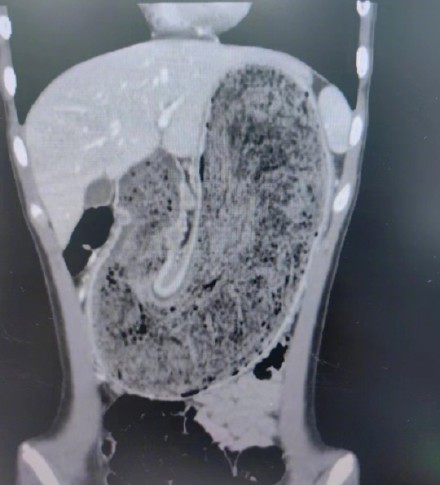

广东东莞一名11岁女孩吃头发三年劝不住,胃里长出巨石,几乎占据了整个胃部。近日因腹痛难忍就医,通过手术取出了一块长38厘米×宽15厘米×厚10厘米的毛发结石。医生表示,女孩吞食毛发的行为,正是身患“长发公主综合征”表现。